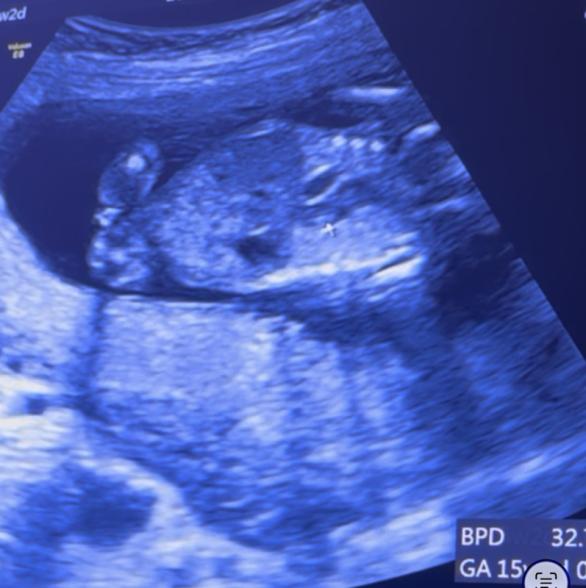

現在15w2dの妊婦です。

今日検診でおそらく女の子かなーと言われましたが

1つ目の写真は今お股になにもないように見えますが

2つ目の写真にはシンボルがついてるのかな?とも思います。

男女どちらの可能性が高いか、

今の時点での高塚先生の見解をお伺いしたいですm(_ _)m